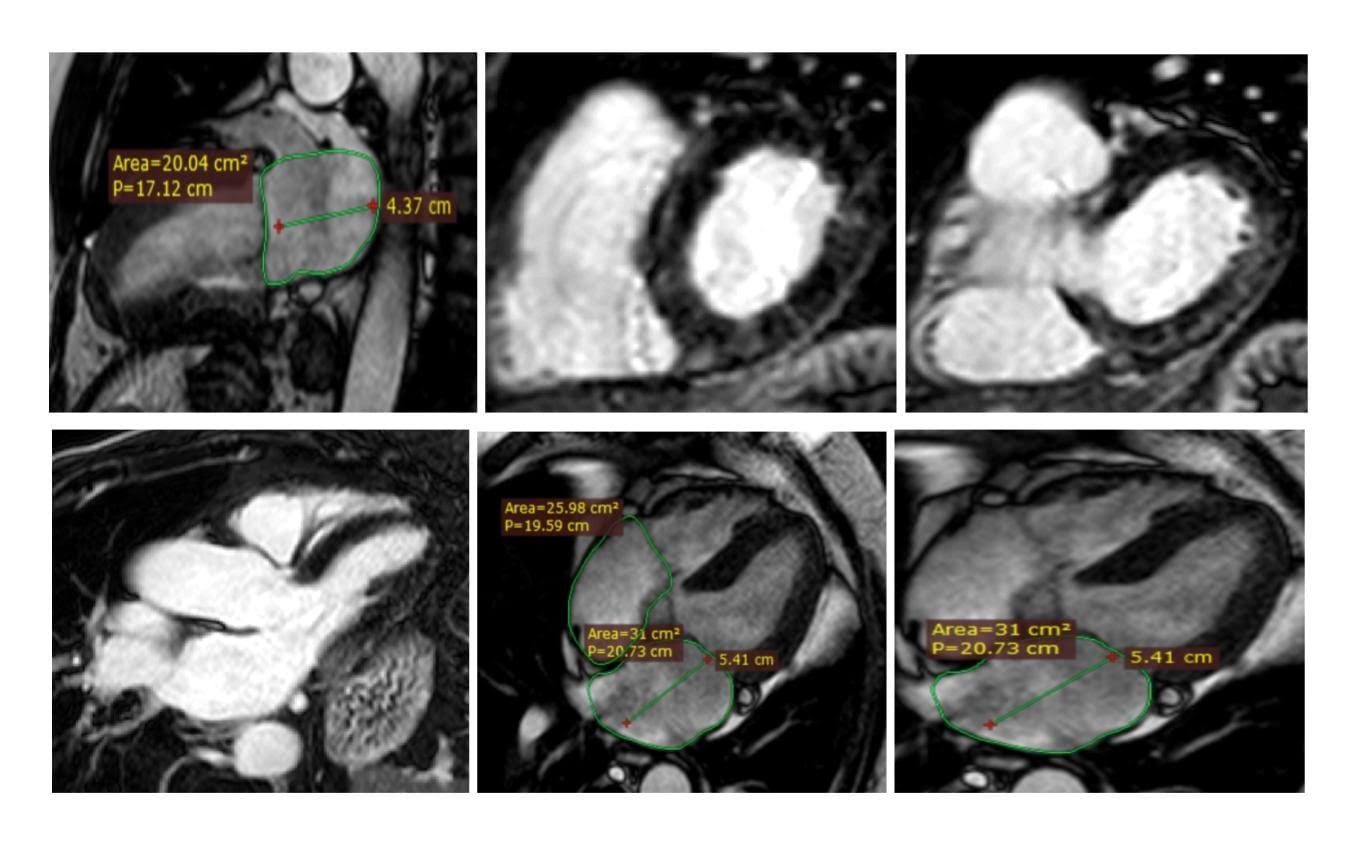

In pratica, attualmente, all’interno dell’attività ambulatoriale dell’Emodinamica di Patti vengono eseguite le seguenti prestazioni specialistiche: 1) prestazioni di I° livello (visita cardiologica con elettrocardiogramma, ecocardiografia color-doppler, test da sforzo su pedana mobile); 2) prestazioni di II° livello (ecocardiografia con mezzo di contrasto ed ecografia transcranica per la ricerca di comunicazioni patologiche all’interno del cuore, ecocardiografia da stress per la studio della cardiopatia ischemica, ecocardiografia trans-esofagea per lo studio di anomalie valvolari ed a supporto di interventi cardiaci strutturali percutanei). Recentemente, disponendo di adeguate risorse professionali e strumentali, gli ambulatori dell’ Emodinamica di Patti sono stati arricchiti di una nuova metodica ad altissima sensibilità e specificità diagnostica (diagnostica di III° livello), ovvero della Risonanza Magnetica Cardiaca eseguita in condizioni basali per lo studio di patologie cardiache tissutali, strutturali e valvolari, con l’obiettivo, entro la fine dell’anno, di estendere la sua applicazione alla ricerca della cardiopatia ischemica durante stress farmacologico (tecnica presente solo in pochi centri del Sud Italia). In un conteso di valida collaborazione tra l’Emodinamica di Patti e le Divisioni di Radiodiagnostica dei PP.OO di Milazzo e Barcellona PG, dirette dal dott. Simone Fogliani e dalla Dott.ssa Francesca Torre, la metodica in oggetto viene concretamente svolta da un team multidisciplinare di Cardiologi e Radiologi presso il Centro di Risonanza Magnetica Nucleare del PO di Barcellona PG, la cui apparecchiatura è dotata di modulo cardiaco Riguardo alla realizzazione di questa rilevante attività diagnostica multidisciplinare, a servizio del vasto territorio Tirrenico-Nebroideo, è doveroso esprimere gratitudine ai Vertici Aziendali dell’ASP Messina, in primo luogo al Direttore Generale dott. Giuseppe Cuccì, per l’imprescindibile supporto tecnico e la fiducia riposta. Un grazie per il contributo organizzativo va anche al direttore Medico del PO di Barcellona PG dott. Giuseppe Cocuzza.